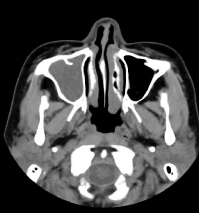

CT検査

内科領域

その他の領域

- その他

- 副鼻腔炎・乳突蜂巣炎(聴器)など